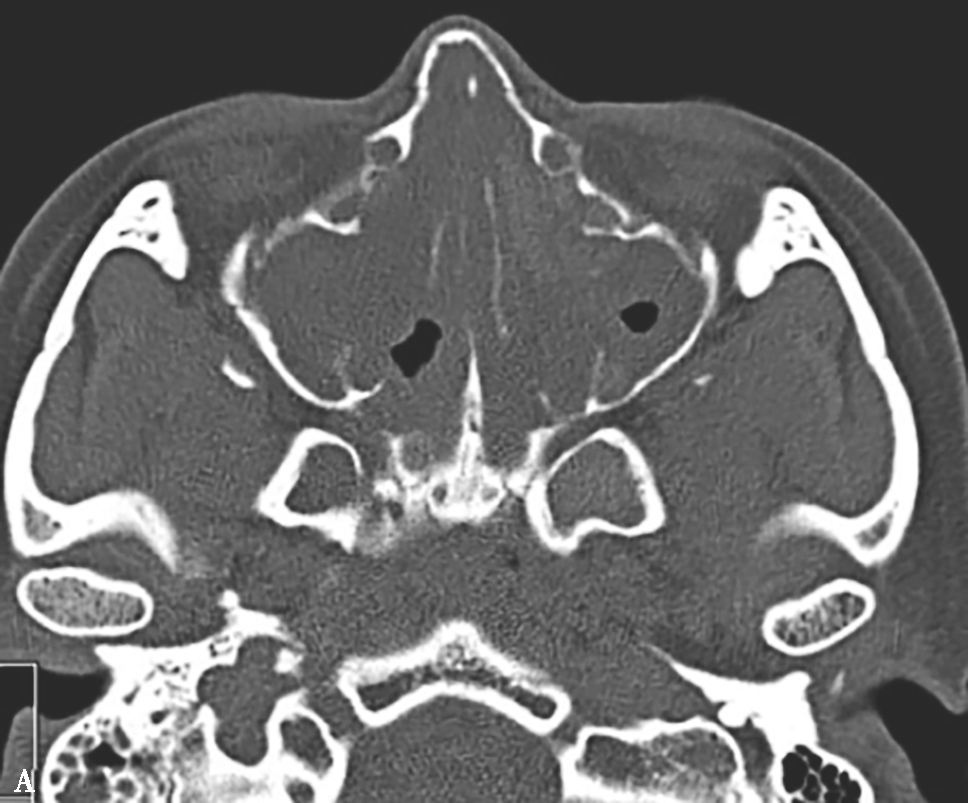

5.CT表现

①平扫表现:早期表现为非特异性黏膜增厚,肉芽肿期表现为实性软组织影,中、下鼻甲可破坏,可有鼻中隔、鼻窦破坏,窦壁骨质增生硬化(图1-3-31A);②增强扫描表现:多为均匀轻、中度强化。

6.MRI表现

早期鼻腔硬结病仅为黏膜增厚,与其他炎性病变不易鉴别。①肉芽肿期T 1 WI和T 2 WI表现为轻度到明显高信号,信号通常不均匀,T 1 WI表现为高信号较有特征性,可提示该病诊断;瘢痕期T 1 WI表现为低或等信号,T 2 WI表现为明显低信号。鼻窦硬结病MRI表现同鼻腔硬结病,但更易向眼眶、颅内、翼腭窝等邻近的结构蔓延,鼻腔通常不受累(图1-3-31B~D)。②增强扫描表现,通常为较均匀的明显强化。

图1-3-31 鼻硬结病

A.横断面CT软组织窗,示鼻中隔前部缺损,鼻腔边缘软组织增厚,鼻背部塌陷,鼻部及双侧颌面部软组织肿胀;另外可见双侧上颌窦炎表现;B.MRI横断面T 1 WI,示鼻腔边缘软组织增厚,呈等信号,上颌窦内病变呈低信号;C.MRI横断面T 2 WI,示鼻腔病变呈等信号,双侧上颌窦增厚的黏膜呈高信号;D.横断面T 1 WI+FS+C,示鼻腔边缘轻度强化,双侧上颌窦黏膜边缘可见强化